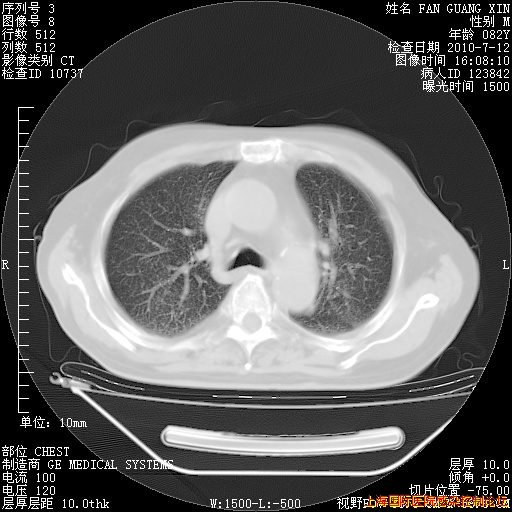

6月12日肺窗

整整相隔30天的肺部CT好像有所好转啊。甲强龙减量第3天,需要观察体温。

海管,自昨日你和我通完话后,不知您岳父消化道症状有无缓解?体温怎样?阅读7.12日胸部ct,个人认为目前激素治疗是有效的,甲强龙减量是适宜的。因在抗痨治疗,需密切观察肝功、肾功能和血常规。不过,老年、长期住院和大量使用激素,很担心菌群失调发生